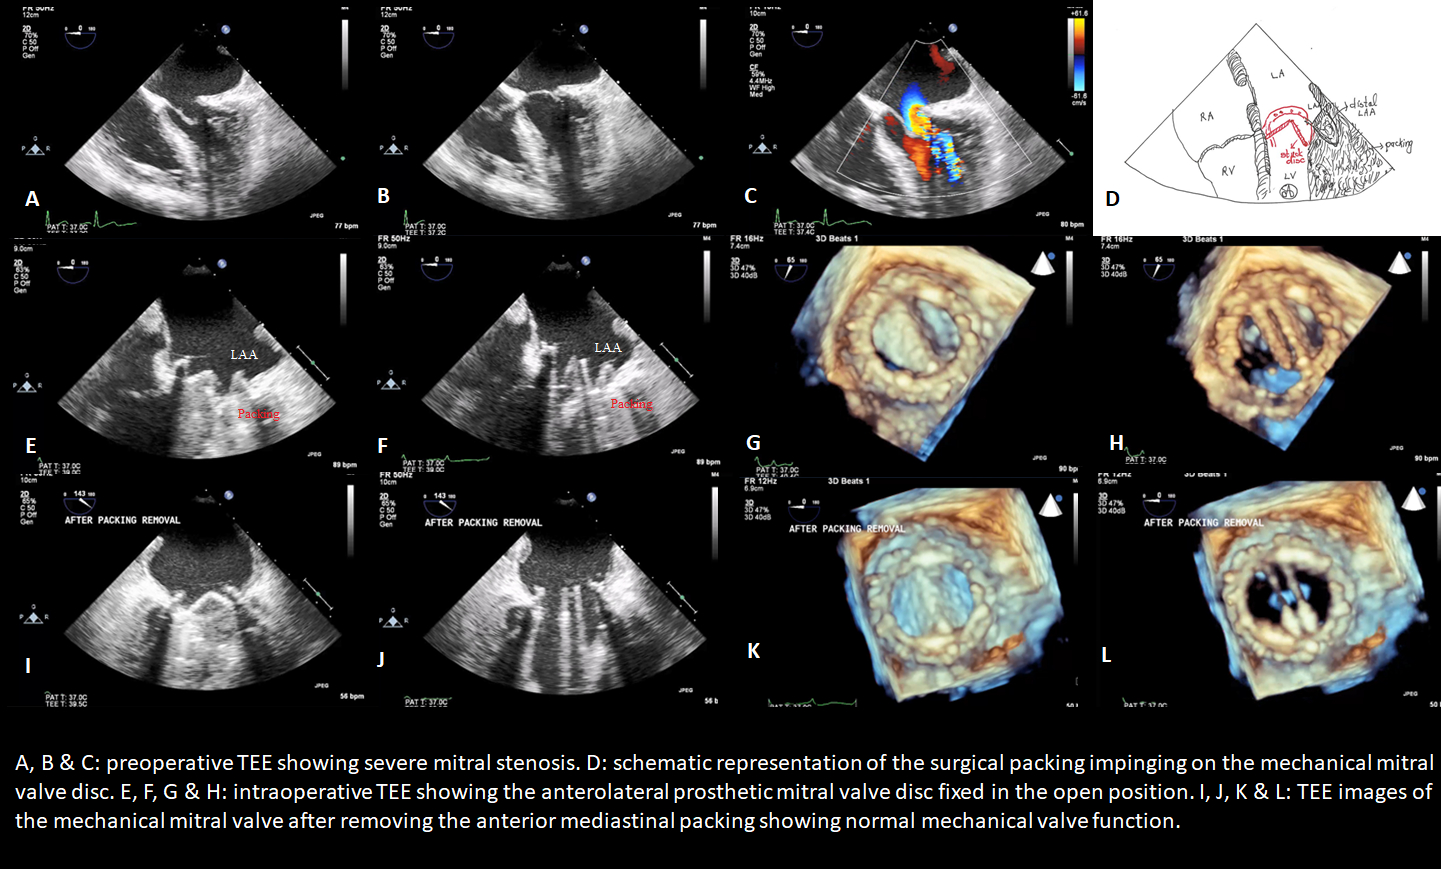

Abstract Body (Do not enter title and authors here): Description of Case: A 44-year-old man with a history of mitral valve prolapse and mitral valve repair with triangular resection and partial annuloplasty ring placement eight years prior to presenting with dyspnea and decreased exercise tolerance. His TTE showed severe mitral stenosis with thickening of the posterior mitral leaflet. A redo sternotomy with mitral valve replacement was planned. Intra-procedurally, it was noted that the previous partial annuloplasty ring was impinging on the proximal portion of the posterior leaflet resulting in restricted motion, there was also fusion of the commissures. The partial annuloplasty ring was removed, and a 25 mm On-X mechanical valve was implanted in the mitral position. At the end of surgery, after the patient was off cardiopulmonary bypass, he developed severe hypoxia, and he was started on inhaled nitric oxide. Due to the concern for poor lung compliance, his sternotomy was not closed, and packing was placed in the anterior mediastinum and covered with an antimicrobial incise drape. In the surgical ICU, he became hypotensive and required ionotropic and vasopressor support. After diuresis, the surgical team decided to bring him back to the operating room on postoperative day 3 with concerns for mechanical valve dysfunction with the possibility of redo valve replacement in addition to closure of the anterior mediastinum and sternum. Intraoperative TEE showed that the anterolateral prosthetic mitral valve disc was fixed in the open position. There was no thrombus seen on the leaflets or the valve apparatus. On removal of the anterior mediastinal packing, the valve leaflet started functioning normally. The chest was closed without the need to redo the mechanical mitral valve.

Discussion: Mechanical valve dysfunction can be either endogenous or exogenous. Our case represents a unique cause of early mechanical mitral valve dysfunction related to external compression by surgical packing impinging on the anterolateral disk inferior to the left atrial appendage from the ventricular side. Intraoperative TEE with 3-D played a vital role in the recognition of this complication and the prevention of redo valve replacement.